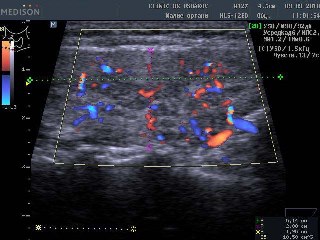

В левой доле (в сосудистом режиме; ЦДК) кровоток восстановился до оптимальной интенсивности ― характерно тоническому (нормальному) состоянию железы |